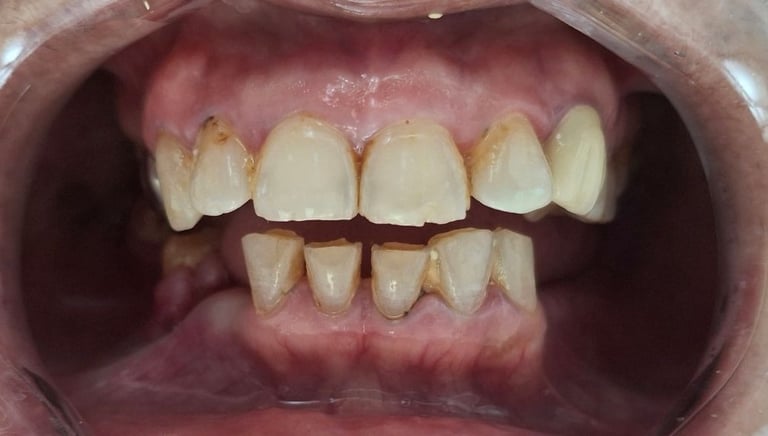

Before

After

All images shown here are real teeth cleaning cases treated at our clinic with patient consent.

Professional teeth cleaning helps remove plaque, tarter, and surface stains that regular at home brushing can not.

At Shree Dental Care, teeth cleaning is performed gently with focus on patient experience, comfort and long term oral health.